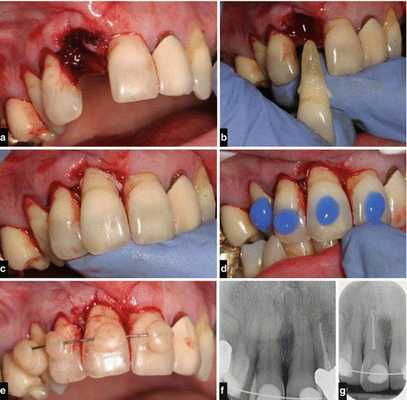

Лечение полного вывиха

В случае полного вывиха зуба, если с момента травмы прошло не более двух суток, проводится его реплантация (установка зуба обратно в лунку) [8] .

Реплантацию проводят по общепринятой методике:

- Травмированный зуб промывают и помещают в изотонический раствор натрия хлорида с антибиотиками до самой операции.

- Если после вывиха прошло не более 10 часов, можно реплантировать зуб, не проводя эндодонтическое лечение (лечение корневых каналов). В таком случае эндодонтическое лечение зуба проводят через 2-3 недели после реплантации, когда становится очевидным приживление зуба.

- Если с момента вывиха прошло более 10 часов, пульпу полностью удаляют, а канал после механической и медикаментозной обработки пломбируют. Зуб после реплантации выводят из прикуса и укрепляют путём шинирования с помощью пластмассовой шины-каппы. Снимают её только через 3-4 недели.

- После реплантации необходимо в течение от одного до двенадцати месяцев проводить рентгенологический контроль. Это позволяет судить о состоянии корня зуба, периодонта и кости.